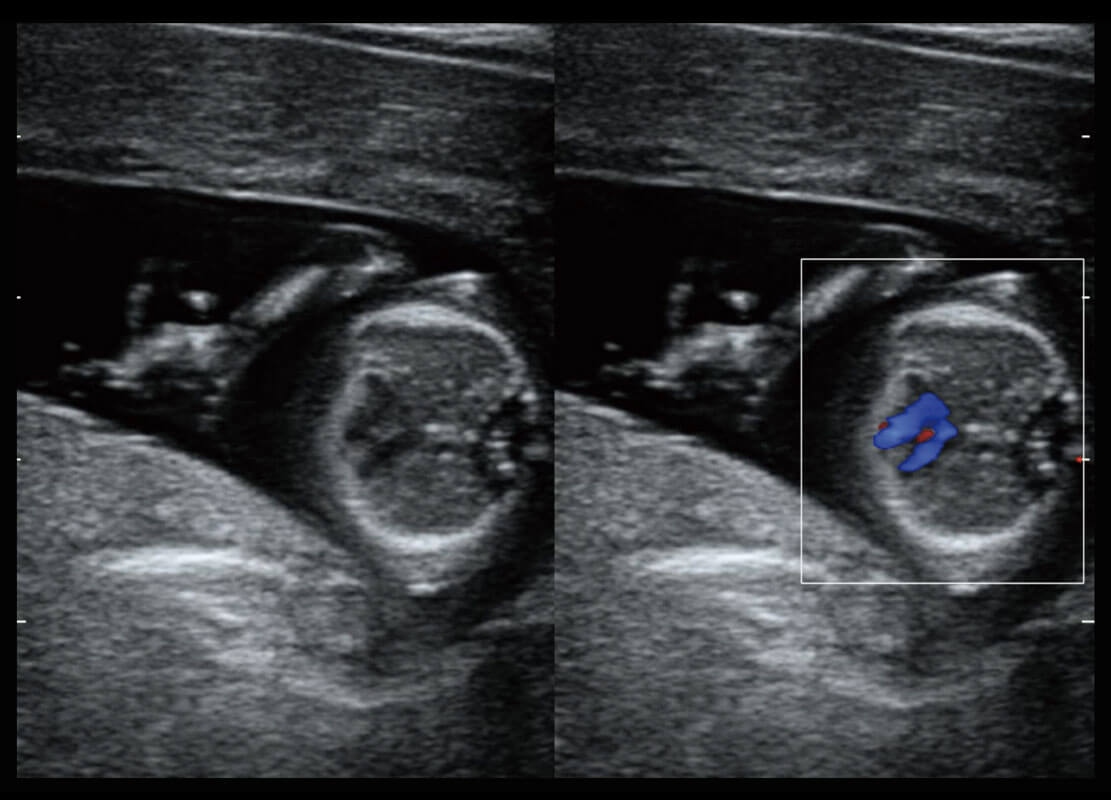

• 新生儿心脏